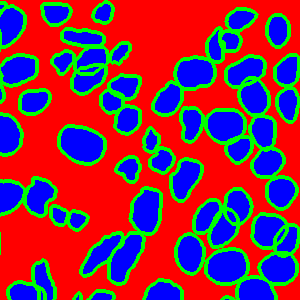

As an essential part of digital pathology, histopathology image analysis is playing increasingly important role in cancer diagnosis, which can provide direct and reliable evidence to diagnose the grade and type of cancer. This paper deals with nuclei segmentation, an important step in histopathological image analysis. The purpose of nuclei semgentation is not only counting the number of nuclei but also obtaining the detailed information of each nucleus. So unlike nuclei detection, here the outputs are the contour of each nucleus instead of only the position of their central points. Hence we can exactly extract each nucleus from the image and make it available for further analysis. For example, the features of the individual nucleus and the distribution of nuclei clusters can be used to grade and classify status of breast cancers [3, 4]. Because of appearance variation such as color, shape, and texture, nuclei segmentation from histopathological images could be very challenging, as illustrated in Fig.1, in which it is very challenging even for human to recognize and segment all nuclei within the images. Fig.1(a) and Fig.1(b) illustrate two histopathological images from different organs. Fig.1(c) and Fig.1(d) are two histopathological images from same organ but have different cancer grade.

Figure 1: (a)Colon cancer (b)Prostate cancer (c)Breast cancer (grade I) (d)Breast cancer(grade III)